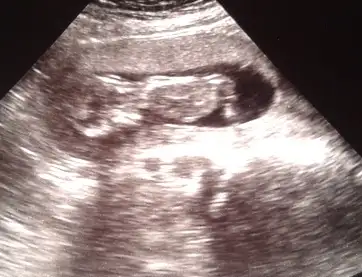

pek tecrubeli degilim..yani cok onemsemeyin ama bence erkekEki Görüntüle 995822 Eki Görüntüle 995823 Eki Görüntüle 995824 Eki Görüntüle 995825

Kizlar kacinci haftada gorunuyor bu nub :)) bizde yarin doktora gidicez anlasilir mi sizce 12 hafta olacak.

Anlasilir.. en iyisi profilden. Bacak arasi vs. Cok heycanliyim bol resim ver bana de :))))

pek tecrubeli degilim..yani cok onemsemeyin ama bence erkek

nub buyuk geldi banaaa..kizlar duzeltsinler ama bence erkek